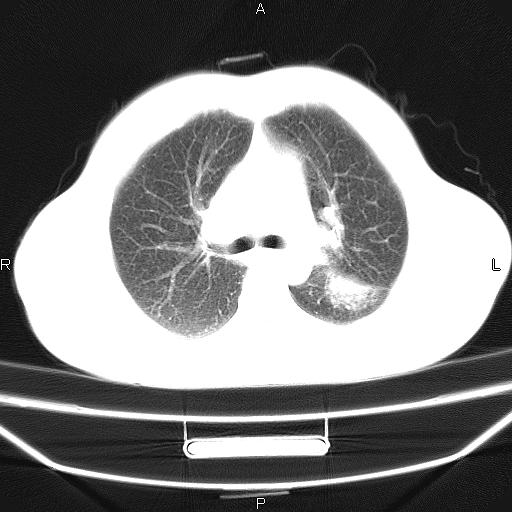

患者,男,40岁。间断发热,咳嗽二十余日。体温最高达38.9° 在当地诊所抗炎治疗三天后体温降至正常,患者自行停药。今又发热。胸片示,左下肺阴影。

左下肺片状高密度影,境界模糊,密度不均,考虑感染性病变可能性大,建议抗炎治疗后复查。左肺门增大,不除外占位性病变,必要时支气管镜检。